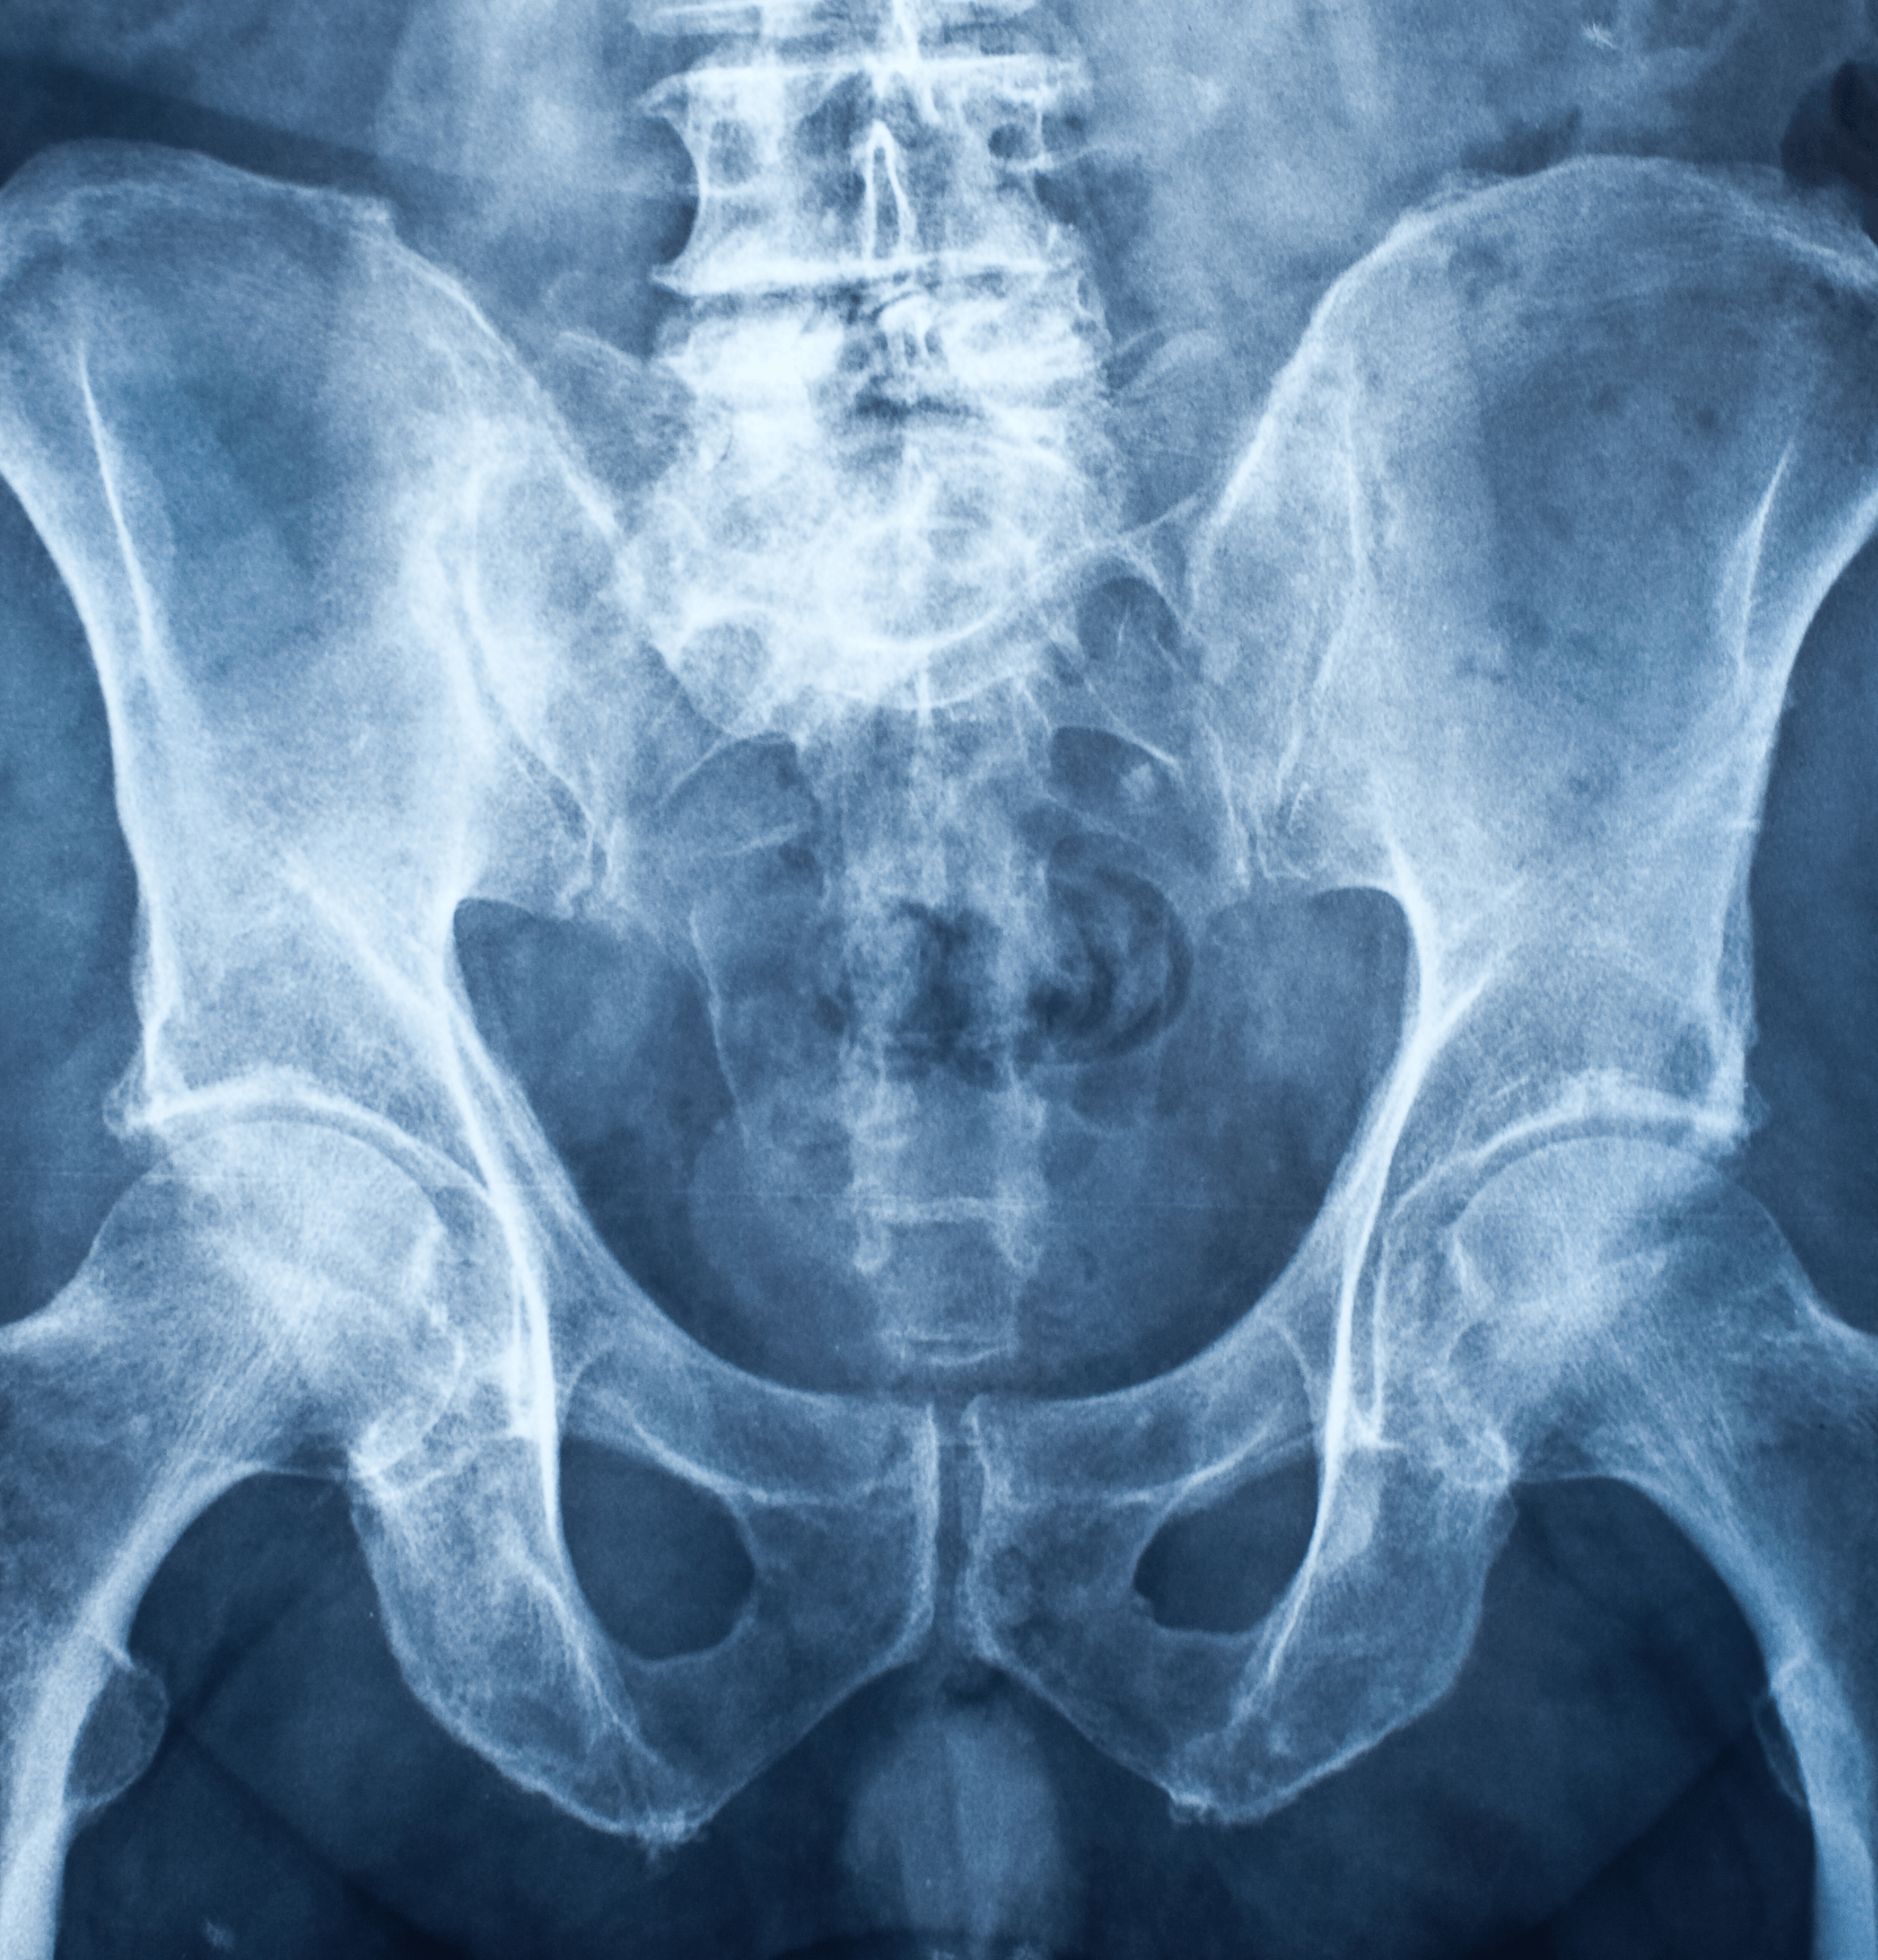

Radiografia bacino

Che cos'è la radiografia del bacino per l'anca?

La radiografia del bacino per l'anca è un esame diagnostico che utilizza i raggi X per creare immagini dettagliate delle strutture ossee del bacino e delle anche.

Questo esame consente di visualizzare chiaramente le ossa dell'anca, il femore, il bacino e le articolazioni, permettendo di identificare eventuali anomalie o lesioni

L'esame radiografico viene eseguito con un fascio di raggi X che attraversa il corpo e si imprime su una pellicola o un rilevatore digitale, creando un'immagine delle strutture interne.